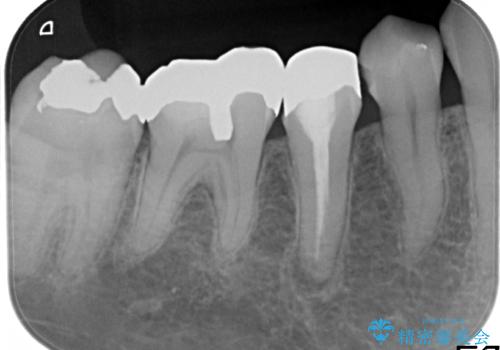

レントゲン上からも、歯の中(根管)が汚れている可能性があることをご説明したところ、根管治療からやり直しをすることになりました。

根管治療は歯内の治療なので患者様には見えない場所ですが、ここが細菌で汚染されると激しい痛みや長引く違和感の原因になります。

当院では、清潔な治療を徹底し、顕微鏡を使用した精密な治療を行っています。